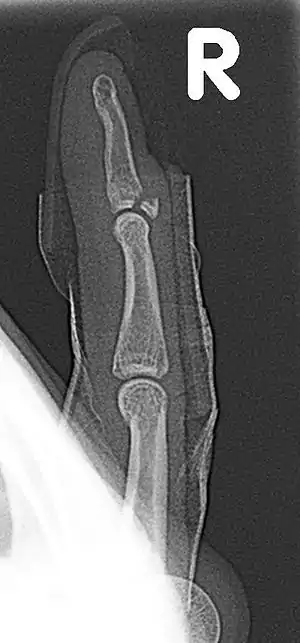

| Fracture of the dorsal base of the distal falange by extensor tendon avulsion (Busch fracture) | |